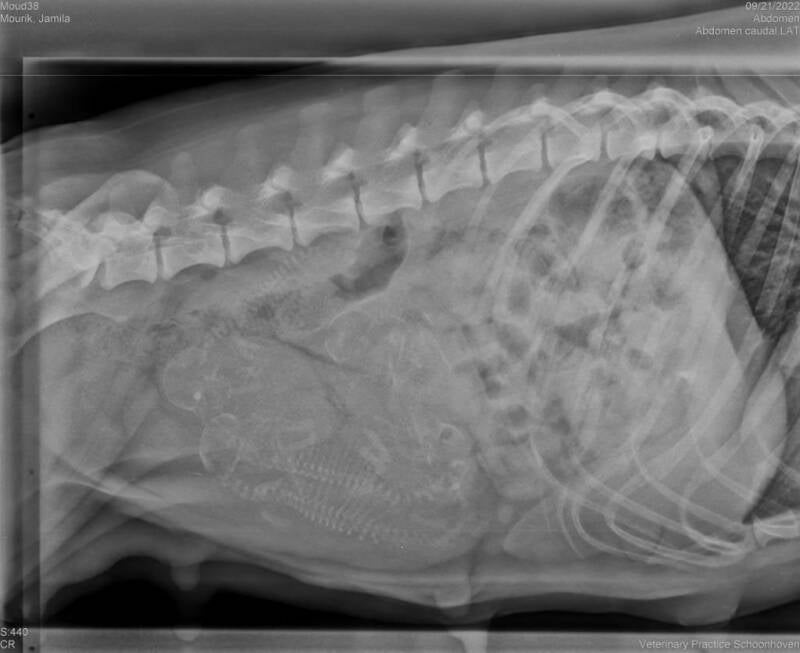

Röntgenfoto

Zie de foto's hieronder voor de röntgenfoto's! Jemila is drachtig van 4 puppy's.